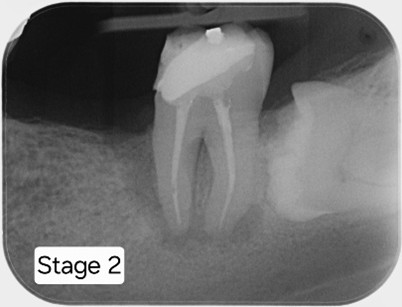

After removing the old crown, the RCT is completed

Posts are placed for a new crown.